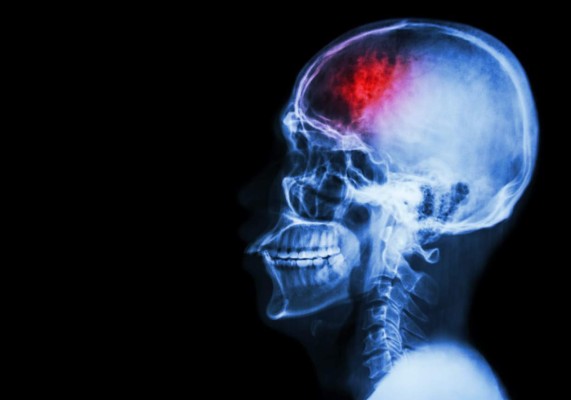

Opinión: Covid-19 y el misterio del ataque al cerebro

Todas estas alteraciones neurológicas parecen indicar que el tejido nervioso estaría más afectado de lo que inicialmente se pensaba. De hecho, un estudio recién publicado en la revista Nature realizado por investigadores de las universidades de Stanford (EE.UU.) y Saarland (Alemania) acaba de demostrar daños significativos en cerebros postmortem de pacientes de covid-19. Estos daños parecen ser similares a los que se observan en enfermos de alzhéimer y párkinson.

El resultado final sería inflamación cerebral persistente, que provoca la muerte de las neuronas y deteriora los "circuitos cerebrales". Estas características de los cerebros de enfermos de covid-19 compartirían similitudes con las halladas en cerebros de personas con alzhéimer y párkinson. Esto es especialmente relevante en neuronas de la corteza cerebral, sobre todo en aquellas regiones implicadas en funciones relacionadas con la memoria, el razonamiento o la toma de decisiones. Muchas de estas alteraciones son las que se producen en la enfermedad de alzhéimer.